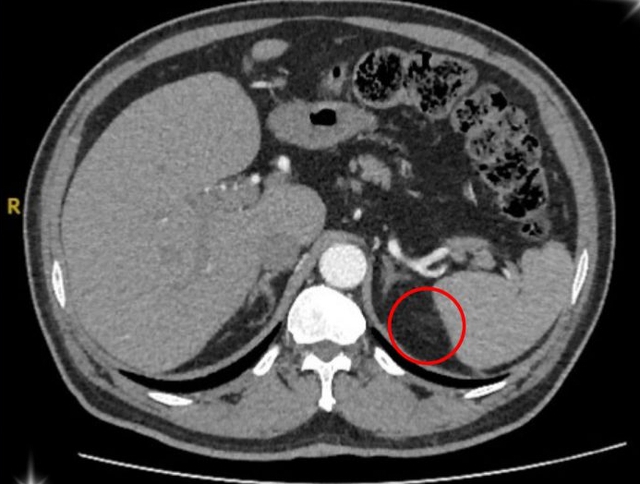

Hình ảnh vùng ổ bụng của bệnh nhân u tuyến thượng thận. Ảnh: BVCC

Sau quá trình kiểm tra kỹ lưỡng, ông T. được xác định mắc phải hội chứng Conn (hay còn gọi là cường Aldosterone tiên phát) – một bệnh lý hiếm gặp do khối u nhỏ ở vỏ tuyến thượng thận gây ra.

Theo BS. Đinh Công Thịnh – Bác sĩ Khoa Ngoại Tiết Niệu, tuyến thượng thận là cơ quan nội tiết nhỏ nằm phía trên thận, đóng vai trò quan trọng trong việc sản xuất hormone giúp điều hòa huyết áp, cân bằng nước, điện giải và kiểm soát quá trình chuyển hóa của cơ thể.

Khi xuất hiện khối u, tuyến này tăng cường tiết ra aldosteron (là hormone giúp điều hòa natri và kali trong máu). Khi lượng hormone này tăng quá mức, người bệnh sẽ rơi vào tình trạng tăng huyết áp kéo dài, hạ kali máu, mệt mỏi, đau đầu, chuột rút, thậm chí rối loạn nhịp tim.